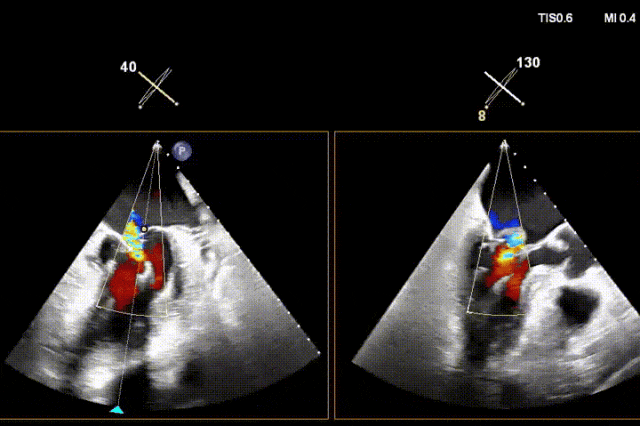

术后即刻反流降为少量,剩余瓣口面积2.57cm²,平均跨瓣压差2mmHg。

术后复查超声心动图显示:二尖瓣轻度返流,三尖瓣中度返流,二尖瓣可见金属夹回声,启闭正常;各心室大小正常,升主动脉不宽,主瓣回声增强,启闭良好;二尖瓣舒张期峰值流速1.4 m/s,功能面积2.1 cm²,跨瓣平均压差约4 mmHg。

术后心功能改善明显:LVdD 46mm,FS 33%,LA 45mm,LVDs 31mm,LVEF 62%。